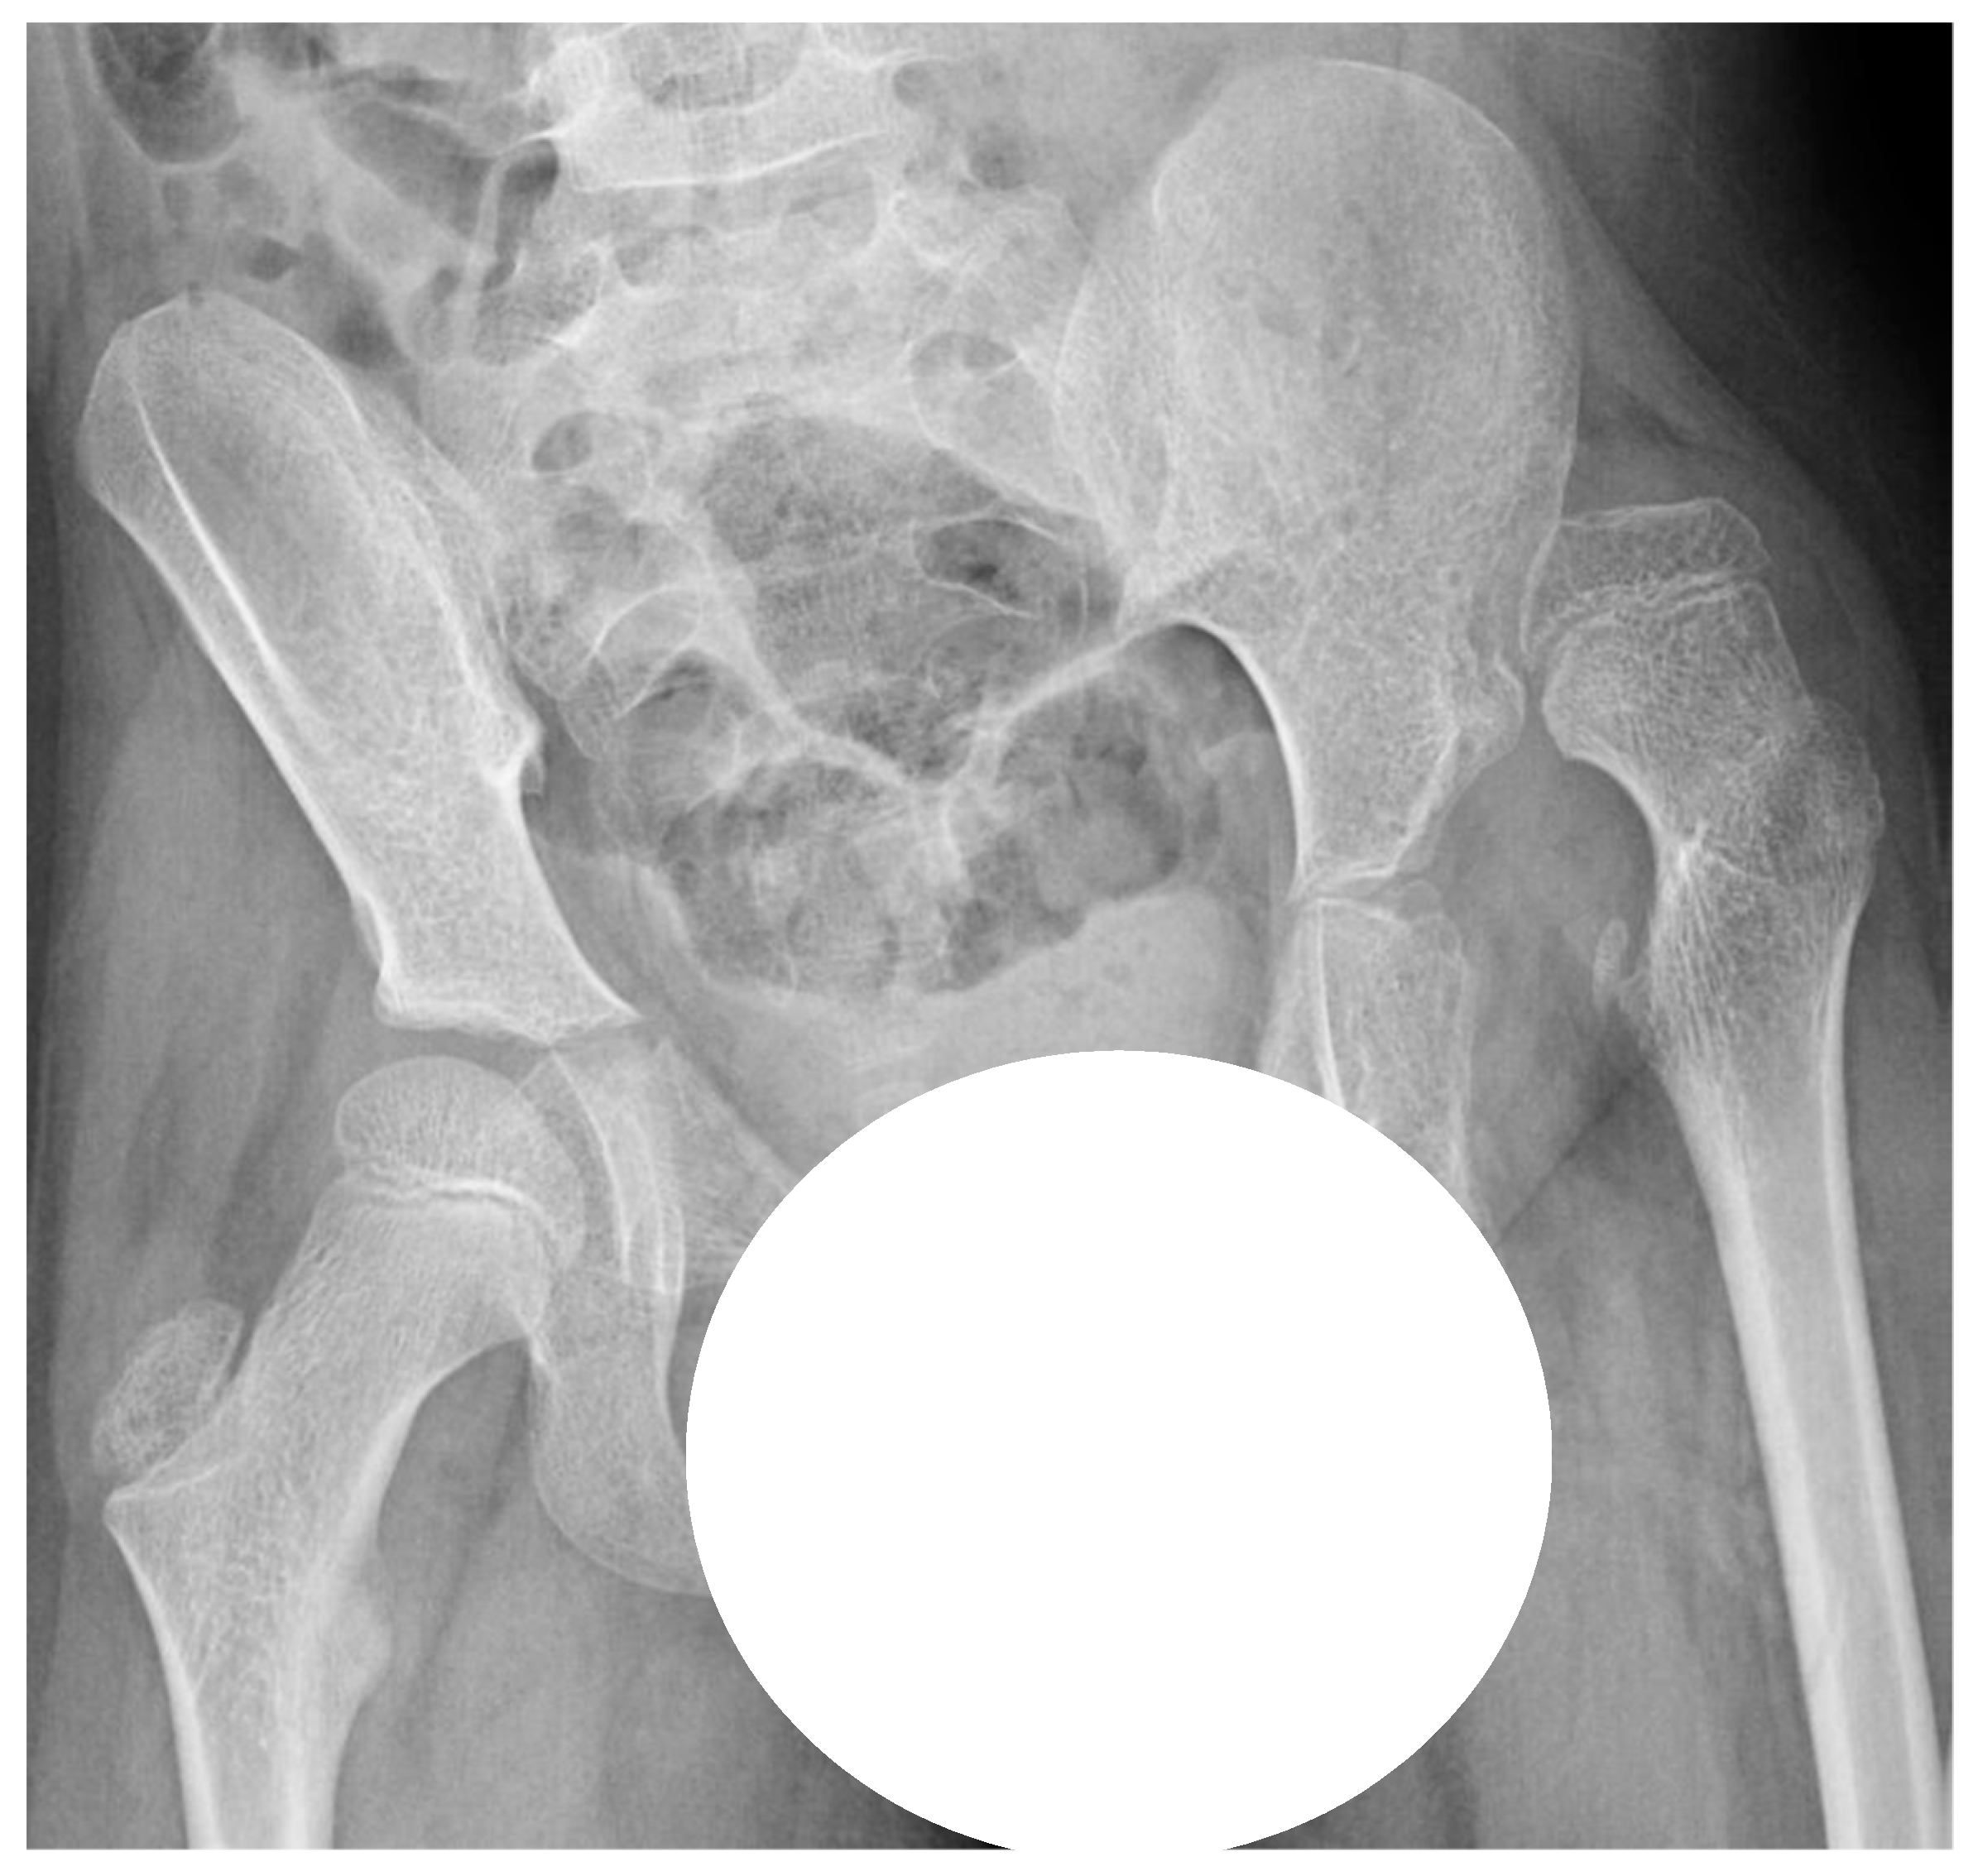

CP is one of the most common lifelong disabilities worldwide, caused by non-progressive brain damage that occurs before the age of two years [10], oftentimes already present in utero. There is great variability in functioning, however, motor function is always affected and challenges in cognition, perception, sensation, behavior, and comorbidities such as epilepsy are frequent [10,11]. Hip displacement, during which the femoral head is laterally displaced within the joint, is common in individuals with CP due to altered muscle forces across the hip joint. Hip dislocation is a severe problem with a high risk of pain, development of severe contractures, windswept deformity, and scoliosis (Figure 1), resulting in problems with posture, sitting, standing, and walking [12,13]. The risk of hip dislocation is estimated to be within 15–20% of the total population of individuals with CP and the risk is highest in those with severe limitations of gross motor function [14]. Hip dislocation in CP, though, is often preventable. Evidence demonstrates that at a population-based level, hip displacement can be prevented if young children with CP are included in surveillance and follow-up programs that include repeated radiographic and clinical examinations and preventative treatments for hip displacement [15,16]. Non-surgical management to prevent hip dislocation includes the positioning of the hip in abduction and extension when lying, sitting, and standing. Surgical treatments of hip displacement in CP, however, consist of adductor–iliopsoas lengthening (APL) or varus derotation osteotomy of the proximal femur (VDRO) and sometimes in combination with pelvic osteotomy. APL is performed primarily on younger children with a lesser degree of displacement, while osteotomy is performed on children with a more severe displacement. The results of APL may also be an indicator of how long the hip displacement was allowed to continue.

Figure 1. Pelvic radiograph of an eight-year old boy with cerebral palsy, left-sided hip dislocation, and pelvic obliquity.